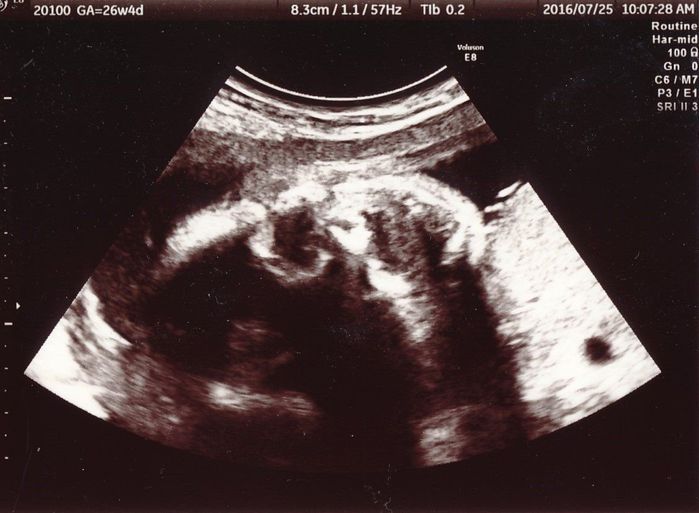

妊娠26週目のエコー写真

これも少し分かりにくいのですが、赤ちゃんの笑顔です。頭が左で、あごが右にあります。中央左寄りにある黒丸が左目で右目は影になってしまっているので分かりません。中央右寄りの黒三角が口で、にっこりと笑っています。